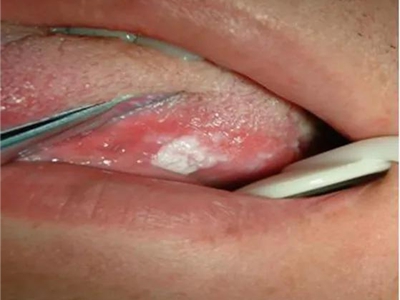

舌头

白点 · 红斑

鹅口疮口腔里面有白色点点和红斑图

鹅口疮患者舌面上形成白色乳凝状、点状或片状物质,这些物质不易刮除,若强行刮除,剥离处局部的黏膜会发生潮红,甚至出现溢血,此外,舌面还可能有灼痛表现。